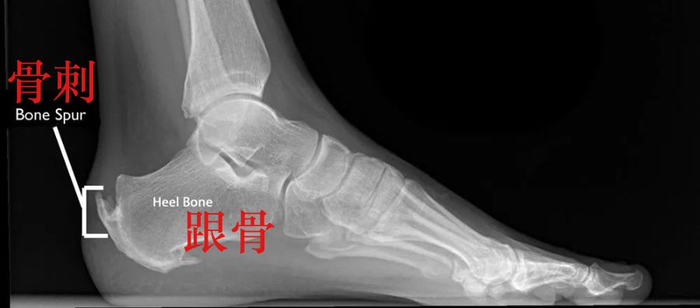

随之而来的是,跟腱附着点炎症病变,肌腱会出现钙化转变为骨质,也就是我们常说的“骨刺”。

骨刺